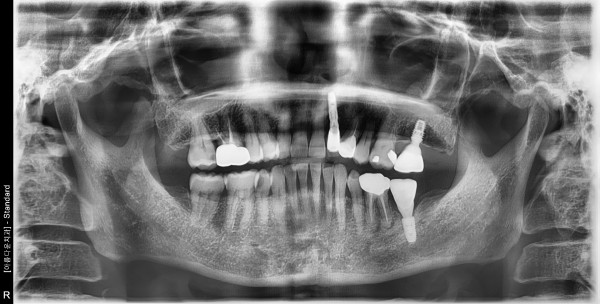

50대 여성 임플란트 식립